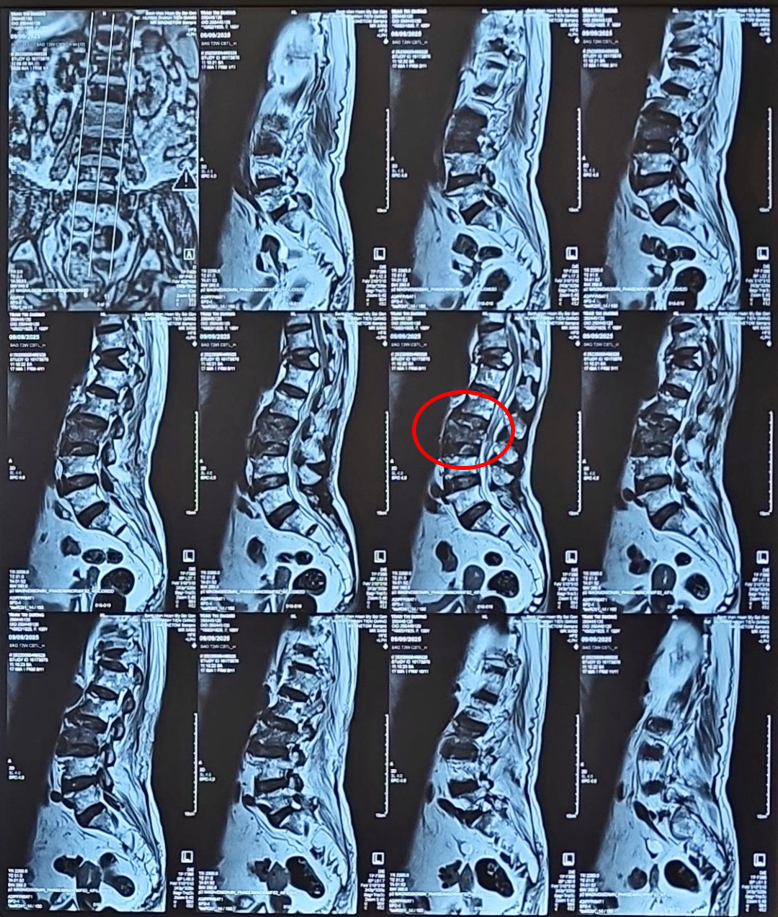

Một tuần sau, khi cơn đau ngày càng dữ dội, gần như không chịu nổi, người nhà đưa bà quay lại bệnh viện hy vọng tìm giải pháp cho bà hết đau. Tại đây, kết quả chụp MRI cột sống ghi nhận rõ hình ảnh gãy xẹp đốt thắt lưng L3 cấp tính, phù tủy xương – nguyên nhân chính gây ra cơn đau.

Hình ảnh MRI cho thấy gãy xẹp nhiều đốt sống trên nền loãng xương nặng, trong đó đốt L3 gãy cấp tính phù tủy xương